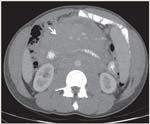

FIGURE 1

Largest Mass on Presentation in a 39-Year-Old Patient With Grade 3 Follicular Lymphoma

A 39-year-old active-duty male with grade 3 follicular lymphoma was transferred from Germany for therapy. He was treated with and responded to 2 cycles of R-CHOP (rituximab, cyclophosphamide, doxorubicin, vincristine, and prednisone), with a 30% decline in the size of his largest mass (Figure 1). Between cycles 1 and 2, the patient developed what appeared to be grade 2 mucositis, dry eyes, and a viral rash (Figure 2). After multiple admissions, evaluations, and biopsies by ophthalmology, dermatology, and oral maxillary facial surgery for continued ocular discomfort, new-onset photophobia, and grossly worsening mucosal ulcerations, the patient was diagnosed with mucosal PNP and lichen planus of the skin. The diagnosis of PNP was not obvious given the nonspecific purple, polygonal, pruritic skin papules (Figure 3), which can also be seen in lichen planus, and a shave biopsy that revealed lichenoid interface dermatitis (Figure 4). Also, the first oral biopsies only demonstrated inflammation.